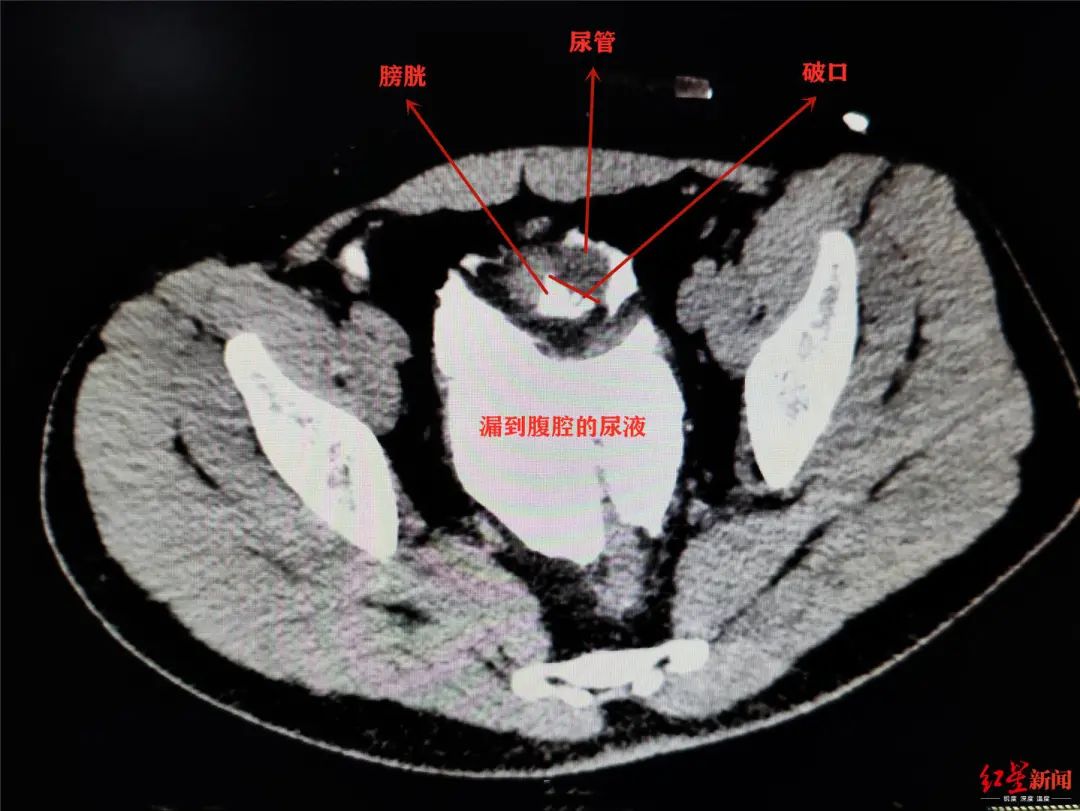

膀胱,尿液,排尿,憋尿,小李,腹腔,袁仁斌,前列腺